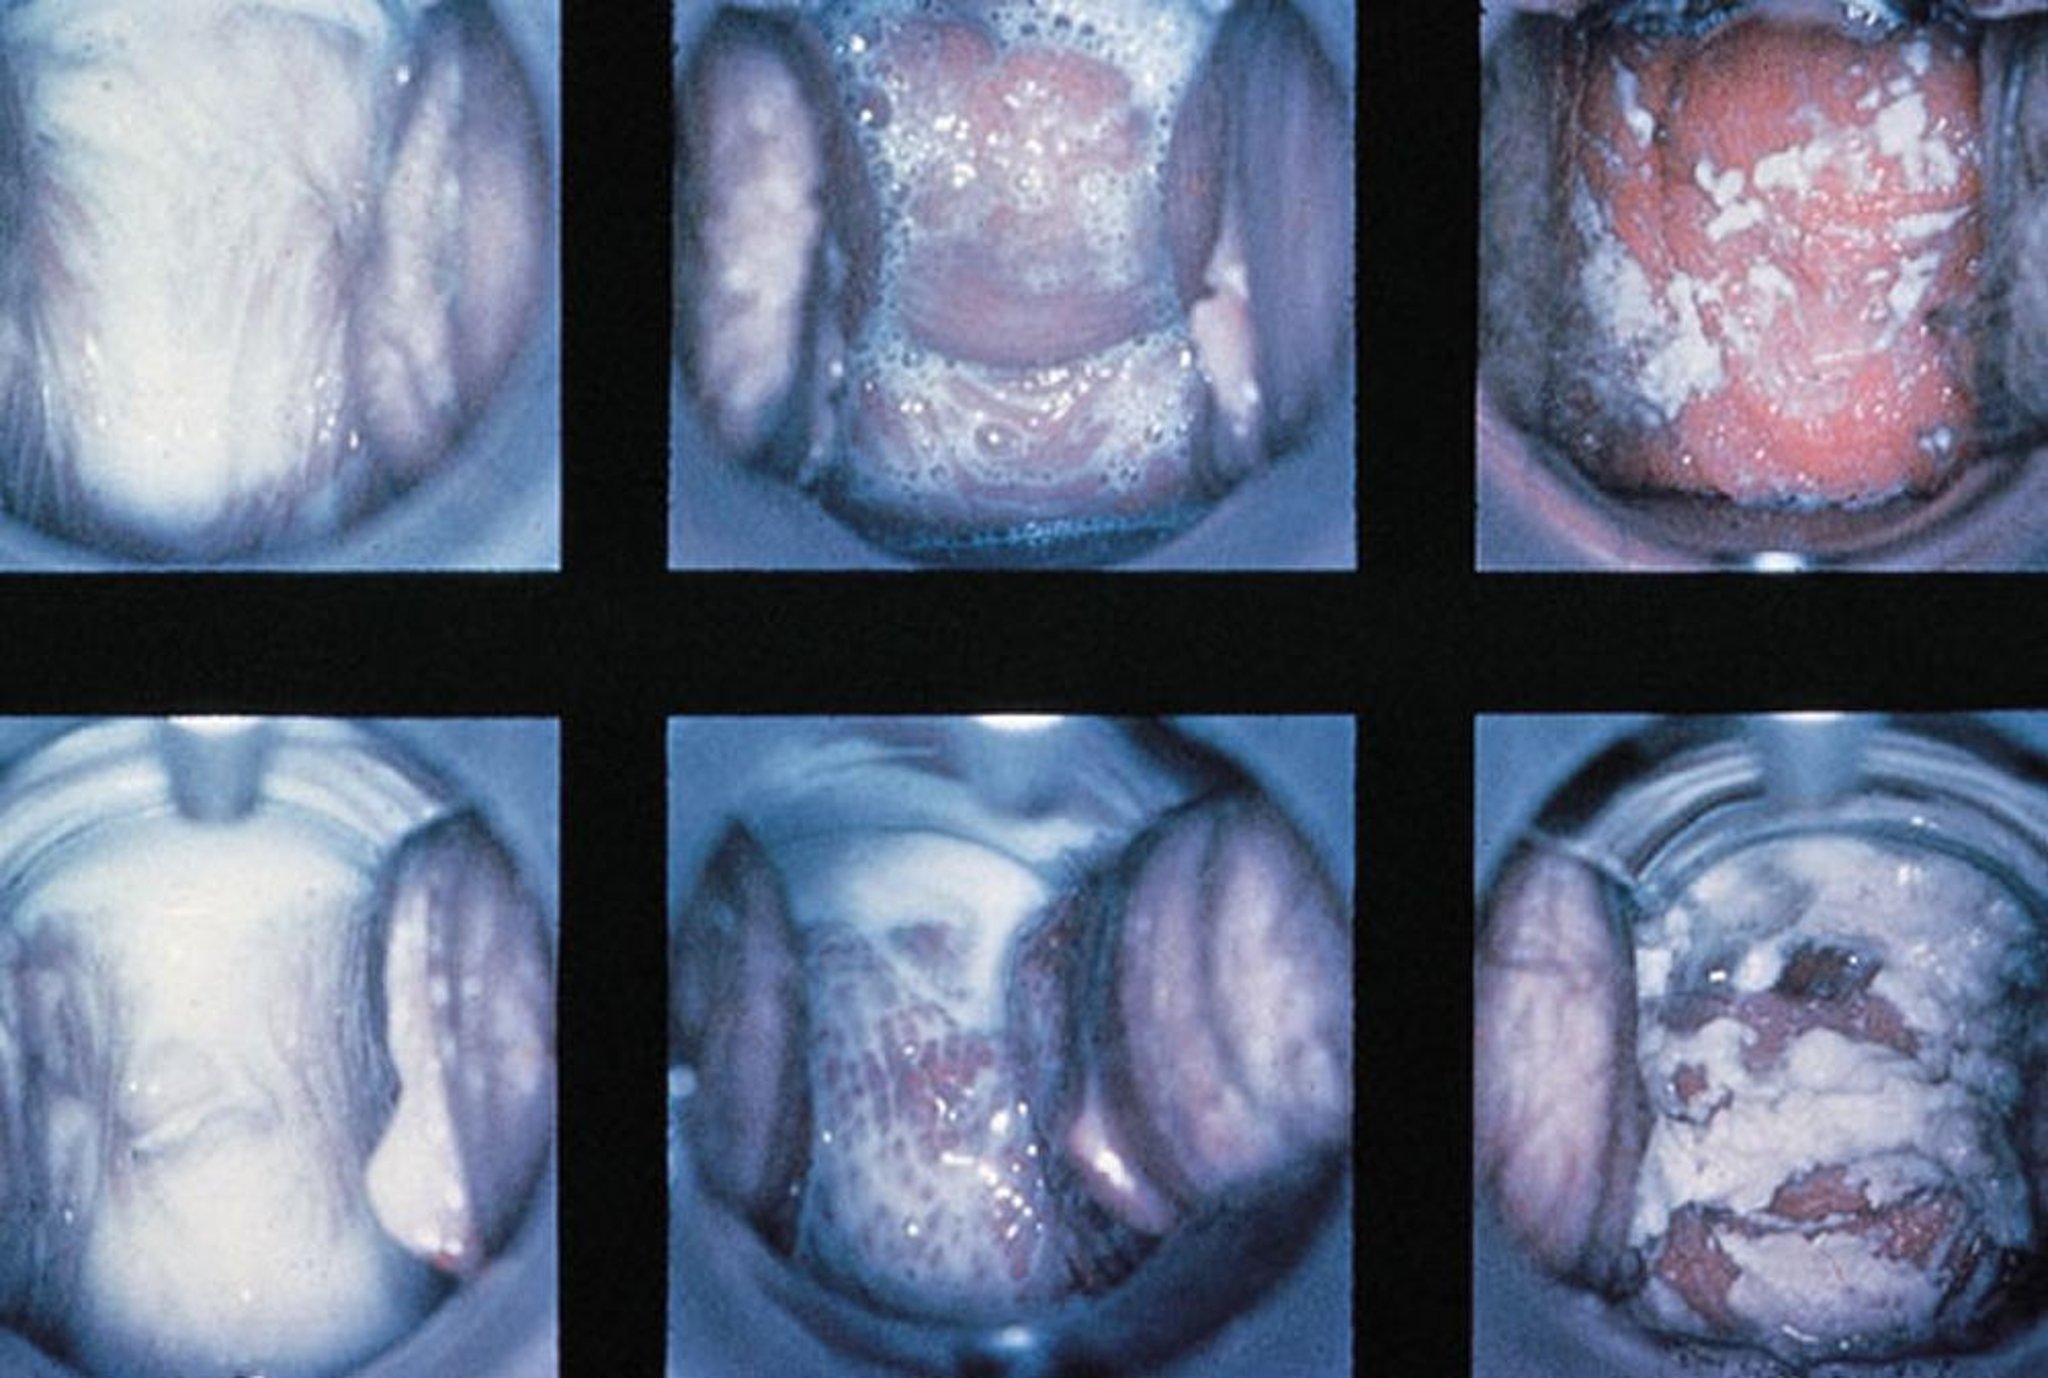

Examen con espéculo en la vaginitis

Hallazgos normales, vaginitis tricomoniásica con secreción espumosa y vaginitis candidiásica con secreción espesa blanca (izquierda a derecha).

By permission of the publisher. From Spitzer M, Mann M. In Atlas of Clinical Gynecology: Gynecologic Pathology. Edited by M Stenchever (series editor) and B Goff. Philadelphia, Current Medicine, 1998. (Courtesy of the International Society for the Study of Vulvar Disease, from the collection of the late Dr. Herman Gardner.)